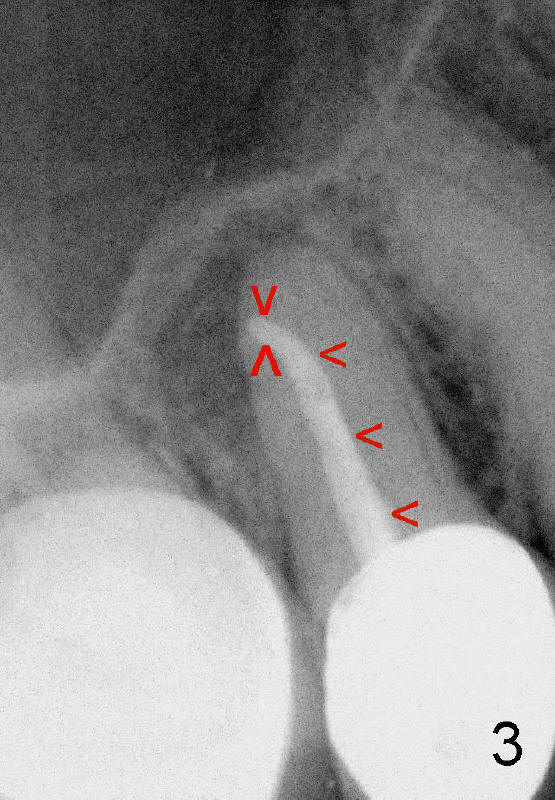

四十八岁俄国女人去年因右上牙痛就诊,右上五(图一:美国称为四号牙)有牙冠修复,叩诊疼痛,牙髓测定死髓牙,术前很难理解为什么根管末端弯曲(图一':红箭头;白箭头代表根尖阴影范围),根管扩大至40/.06(rotary file),插入同一号牙胶尖(图二箭头),好像挺接近弯曲根管顶端,但是离根尖还有一些距离,从牙冠打洞,里面一片漆黑,使用两倍半放大镜(loops),也无能为力,最后完成根管充填(图三),看上去挺不错,顺着弯曲根管走(箭头),有些得意洋洋,最末端部分(上下箭头之间)可能被糊剂充填。欣慰的是术后疼痛消失,一年后病人因右下桥松动而再次就诊,检查表明七断裂需要拔牙,植牙,由于下牙槽神经在根尖片中看得不清楚,她牙齿问题很多,便拍摄全口CT。右上五CT显示根尖阴影好像没有减少多少(图四箭头,与图一',图二,图三对比),所以根管末端弯曲有一定特殊意义,那是什么呢?